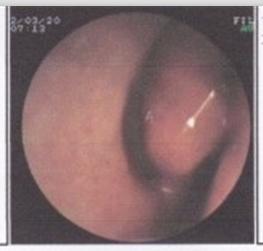

鼻息肉术后护理注意事项!贵阳耳鼻喉医院专家指出,鼻息肉有着顽强的生命力,对于鼻息肉这样的疾病,不仅仅是手术过后就没事了,手术后的护理、复查等等一系列的都是十分关键的事项,下面就来给大家介绍一下鼻息肉手术后注意事项有哪些。

鼻息肉术后护理注意事项

鼻息肉术后护理注意事项: